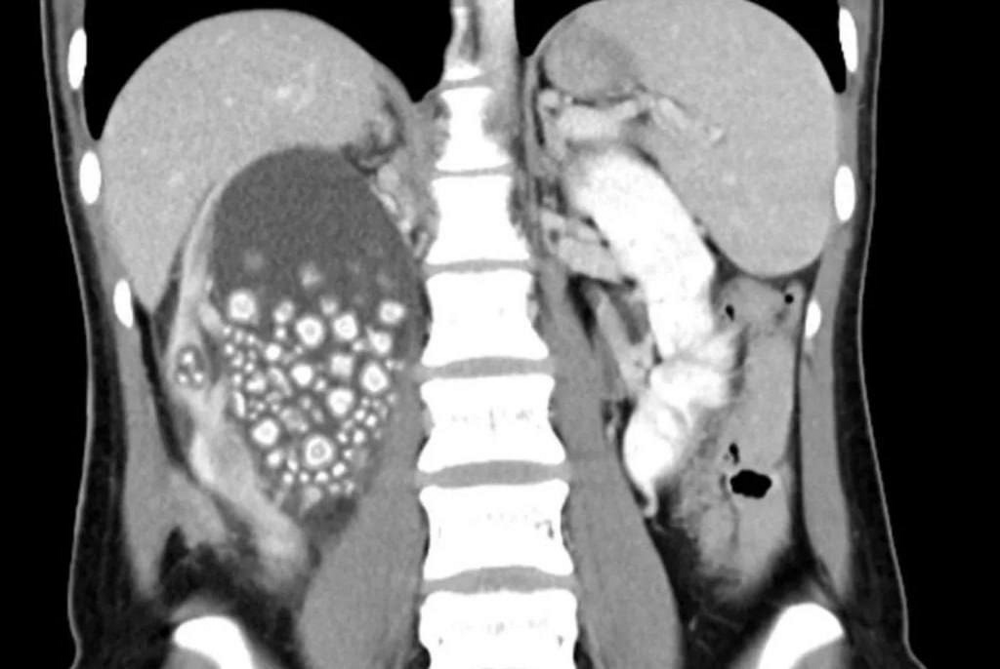

After a young patient was x-rayed, it was discovered that one of her kidneys was completely filled with hundreds of tiny kidney stones. Well, Xiao herself said that she did not abuse soda, drank only sweet drinks and juices and did not drink water at all, believing that there was already enough fluid in her body.

Doctors managed to save her kidney by removing more than 300 mineral formations ranging in size from 0.5 cm to 2 cm in diameter.